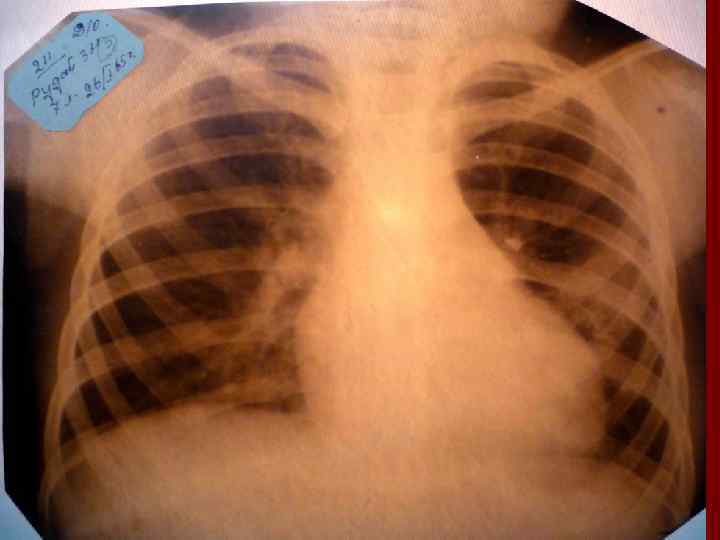

Долевая пневмония характеризуется лобарным пневмоническим инфильтратом. Крупозная ( пневмококковая) пневмония диагностируется прежде всего по клиническим данным. Крупозная пневмония сохраняет свою типичную картину пневмококковой пневмонии: острое начало с характерными клиническими данными, циклическое течение, несклонность к деструкции, гомогенной и лобарной инфильтративной тенью при рентгенологическом исследовании. Вместе с тем, широкое использование антибиотиков способствовало значительному снижению числа крупозных пневмоний у детей. Интерстициальная – редкая форма пневмоний, при которой оказывается поражен прежде всего интерстиций. Как правило, интерстициальная пневмония обусловлена вирусами, пневмоцистами, внутриклеточными микроорганизмами и грибами.

Морфологическую форму пневмонии определяют по клинико – рентгенологическим данным: выделяют очаговую, очагово – сливную, долевую ( крупозную), сегментарную и интерстициальную пневмонии. Очаговая – наиболее распространенная форма. Пневмонические очаги чаще бывают размером 1 см и более. Очагово – сливная – инфильтративные изменения в нескольких сегментах или во всей доле легкого, на фоне которых могут быть видны более плотные участки инфильтрации и/или полости деструкции. Сегментарная – в процесс вовлекается весь сегмент, который, как правило, находится в состоянии гиповентиляции, ателектаза. Морфологическая картина воспаления при очаговых и сегментарных пневмониях связана с первичным инфекционным воспалением в бронхах, что дает основание отнести эти варианты поражения легочной ткани к бронхопневмониям, нередко сопровождающихся бронхообструктивным или бронхообтурационным синдромами. В настоящее время данный тип пневмоний у детей встречается наиболее часто.